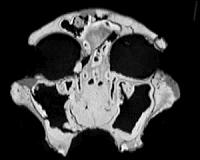

CT study of early humans reveals evolutionary relationships

CT scans of fossil skull fragments may help researchers settle a long-standing debate about the evolution of Africa's Australopithecus, a key ancestor of modern humans that died out some 1.4 million years ago. The study, to be published in the Proceedings of the National Academy of Sciences, explains how CT scans shed new light on a classic evolutionary puzzle by providing crucial informat ... read more